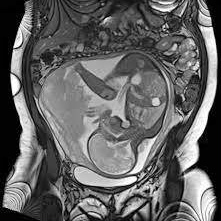

Resonancia nuclear magnetica obstetrica. EN. Codigo 883442 (2022)

Medellin, Sabaneta

$890000

Medellin, Barrio Prado Centro: Calle 59 # 50 A - 14

Sabaneta, Carrera 48 # 50 sur 128. Al interior del Centro Comercial Mayorca Mega Plaza